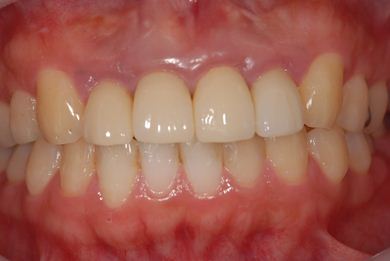

治療後

• 治療後